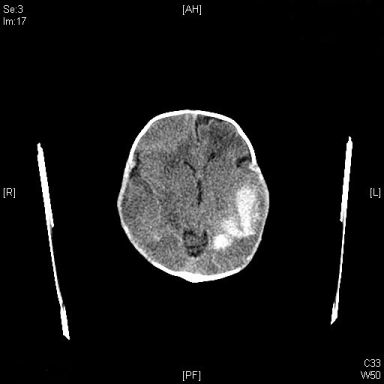

CT brain

A large intraparenchymal hemorrhage in the left temporoparietal lobes, diffuse hypodensities of cerebral parenchymal. Multiple extra-axial fluid collection likely subacute hemorrhage along convexity of both cerebral hemispheres (Figure 2).

Figure 2: CT image of infant head, a coronal view demonstrate large intraparenchymal hemorrhage located at the left temporo-parietal lobes diffuse hypodensities of cerebral parenchymal. View Figure 2